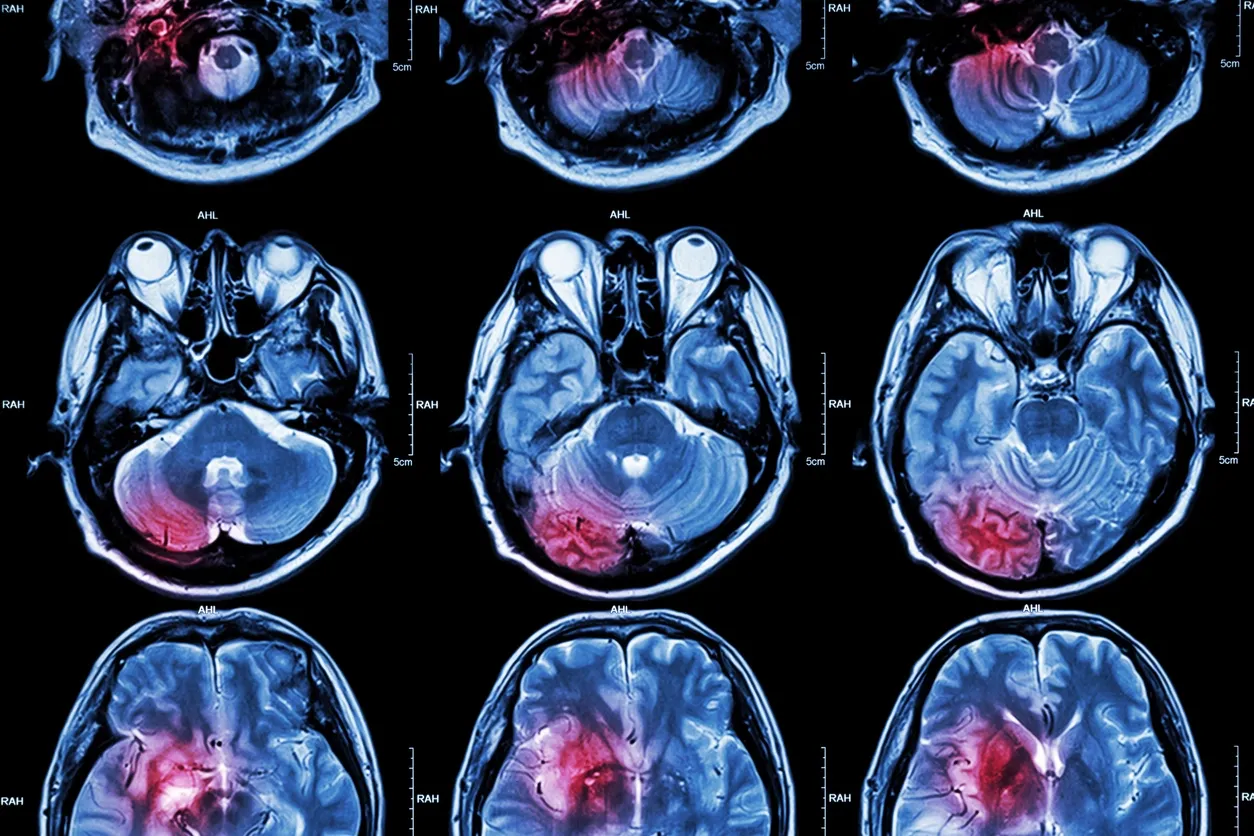

Estudios confirman la idea de que el dolor físico y el emocional comparten algunos mecanismos neurales subyacentes. Así, el dolor físico que experimentamos al golpearnos podría activar los mismos mecanismos de dolor que la pérdida o ruptura de un vínculo emocional. En efecto, imágenes de nueroanatomía han comprobado que las mismas zonas del cerebro que se activan al experimentar dolor físico, se activan con el dolor emocional y social -como el que genera la exclusión- (11) .